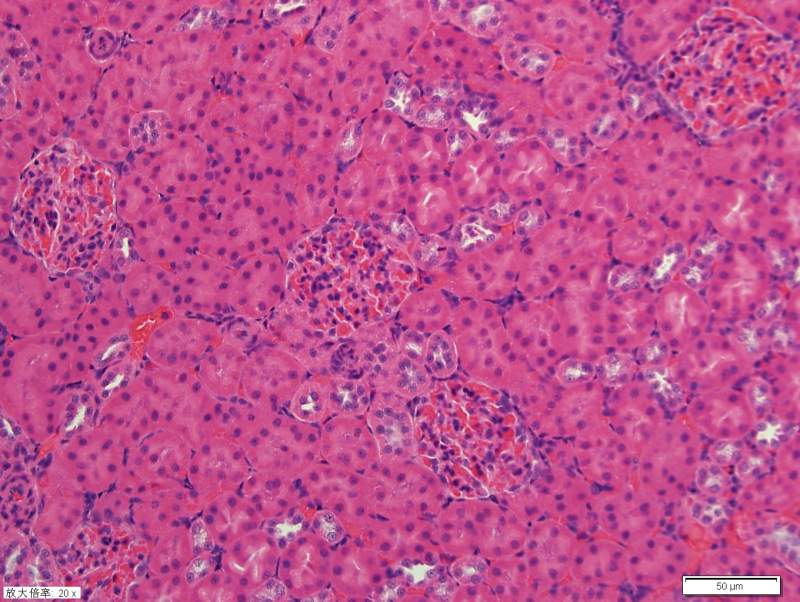

请教各位高手关于肾脏HE染色 已有1人参与